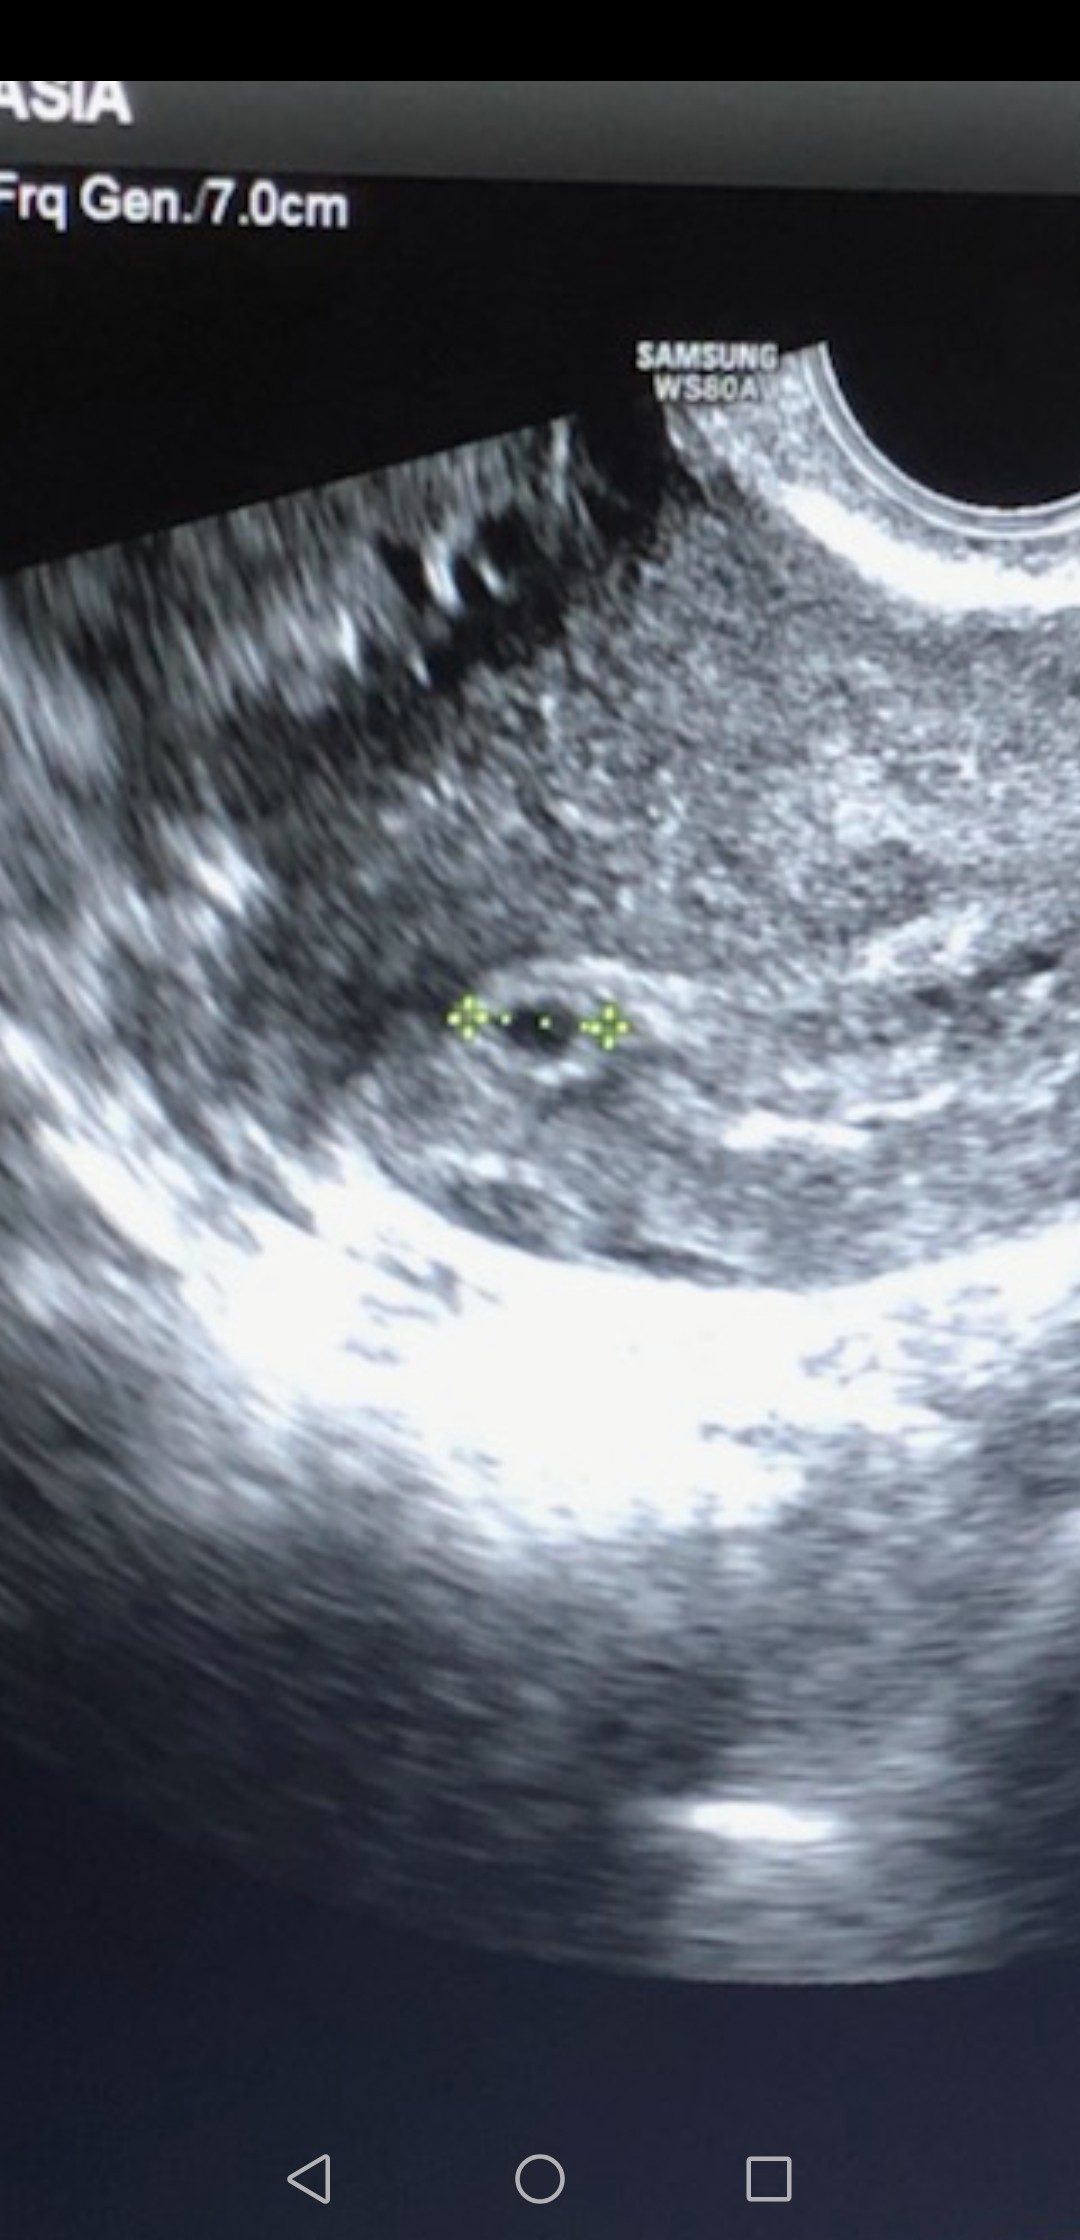

• Screenshot_20191031_152217_com.android.gallery3d.jpg

Screenshot_20191031_152217_com.android.gallery3d.jpg

235,7 KB · Wyświetleń: 112